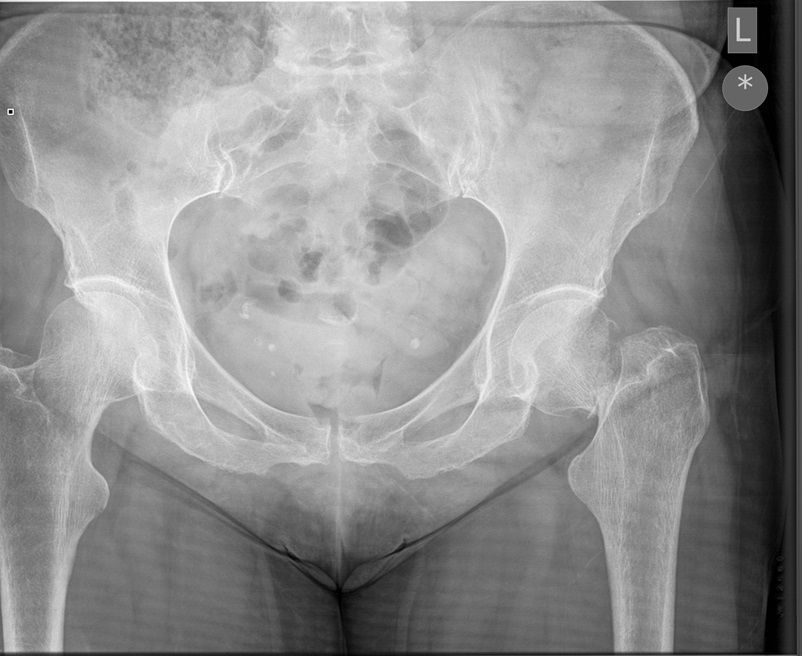

I was hoping you would partake in a study we are doing. We want to establish if there is any bias when deciding an operation based on the radiograph. We understand that the NICE guidelines state that the patient management for hip surgery should not be based on the radiographic findings; rather it should be based on defined criteria. However with that aside what we are requesting is that you look at the film + decide what operation either THR or Hemiarthroplasty. Click the dot + select answer.

Question 1

Question

Which operation would you chose?

Answer

• THR

• Hemiarthroplasty